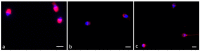

Swim-up selected human sperm were incubated with 7 ng F4-neuroprostanes (F4-NeuroPs) for 2 and 4 h. Sperm motility and membrane mitochondrial potential (MMP) were evaluated. The percentage of reacted acrosome was assessed by pisum sativum agglutinin (PSA). Chromatin integrity was detected using the acridine orange (AO) assay and localization of the ryanodine receptor was performed by immunofluorescence analysis. Sperm progressive motility (p = 0.02) and the percentage of sperm showing a strong MMP signal (p = 0.012) significantly increased after 2 h F4-NeuroP incubation compared to control samples. The AO assay did not show differences in the percentage of sperm with dsDNA between treated or control samples. Meanwhile, a significantly higher number of sperm with reacted acrosomes was highlighted by PSA localization after 4 h F4-NeuroP incubation. Finally, using an anti-ryanodine antibody, the immunofluorescence signal was differentially distributed at 2 and 4 h: a strong signal was evident in the midpiece and postacrosomal sheath (70% of sperm) at 2 h, whereas a dotted one appeared at 4 h (53% of sperm). A defined concentration of F4-NeuroPs in seminal fluid may induce sperm capacitation via channel ions present in sperm cells, representing an aid during in vitro sperm preparation that may increase the positive outcome of assisted fertilization.